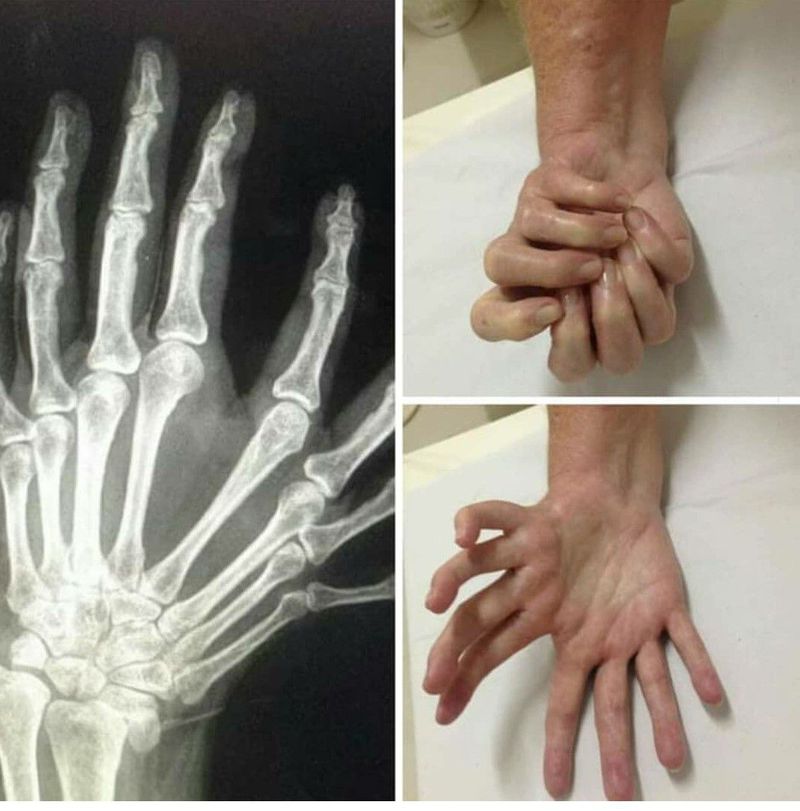

Name the syndrome

Polydactyly...

ulnar dimelia

Mirror hand syndrome